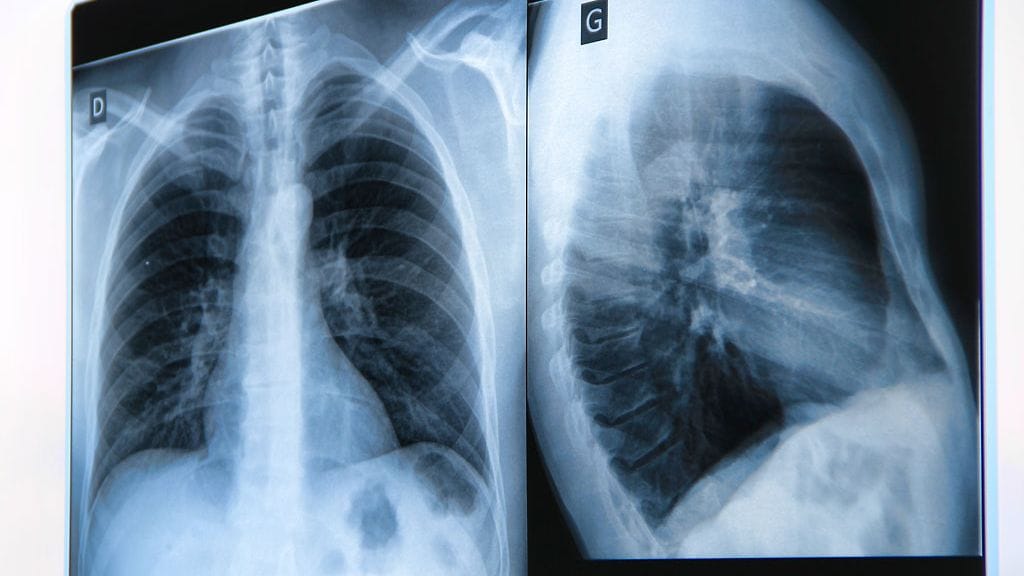

Vuonna 2011 kolmekymppinen Jonna muutti poikaystävänsä luo Saksaan. Tuore avomies totesi heti, että Jonnan selkä on vino. Jonna meni tapaamaan lääkäriä, joka otti selästä röntgenkuvan. Pian Jonna sai kuulla, että hänellä on Scheuermannin tauti.

Hän toteaa, että tauti on helposti hoidettavissa oireiden ja röntgenkuvan perusteella. Jos diagnoosi tehdään ajoissa, voidaan selkäranka saada kasvamaan oikeaan asentoon fysioterapian ja tukikorsetin avulla.

Ja nyt riitti yksi ainoa rivilääkärin määräämä röntgenkuva selvittämään, mikä Jonnaa oikeasti vaivaa.